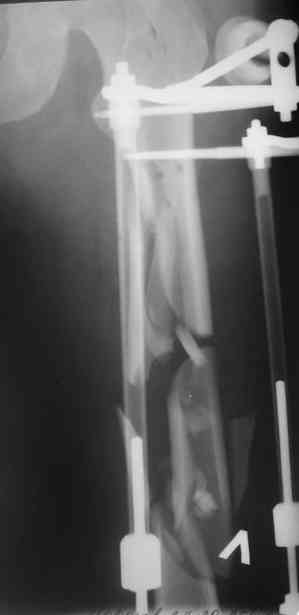

А в чем проблемы? Пример в приложении.

Насчет снимка Вами представленного - смотрится оч красиво, еще бы на функцию узнать...

I> Насчет снимка Вами представленного - смотрится оч красиво, еще бы на

I> функцию узнать...

В приложении функциональные снимки в 3 мес. и в 1 год.